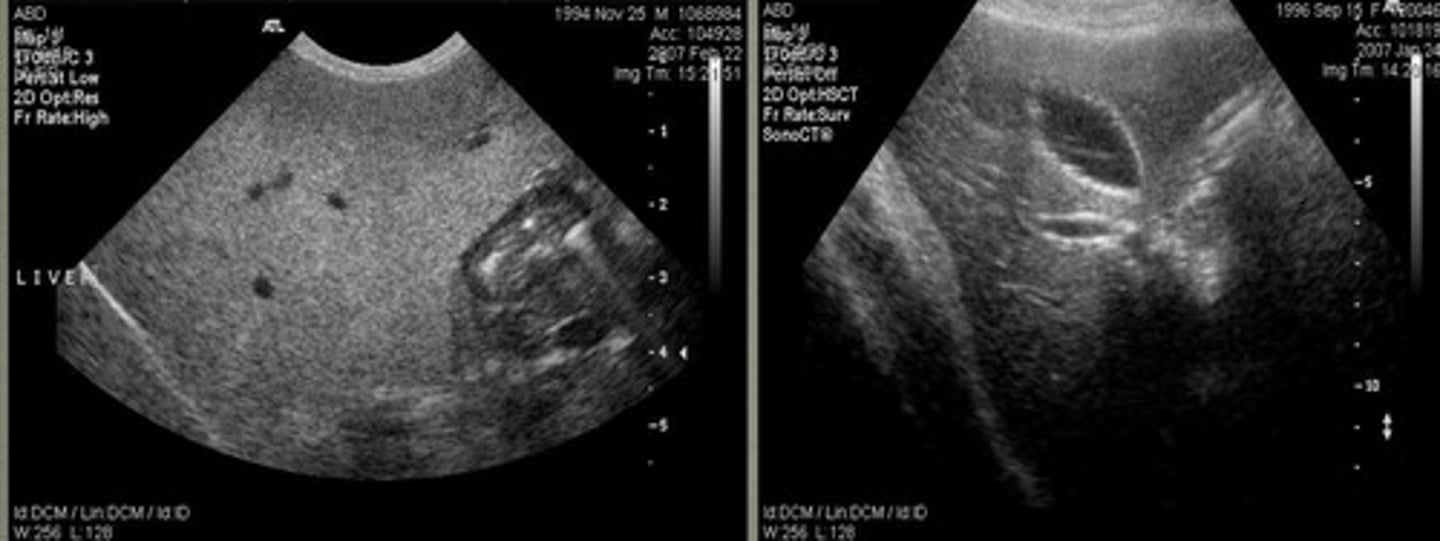

what part of the liver is this showing?

left caudal border of the liver

what part of the liver is this showing?

right caudal border of the liver

what part of the liver is this showing?

which of these US images of the liver is abnormal?

diaphragm

what is the red arrow pointing to in the left image?